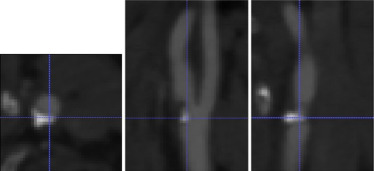

Se aplica la metodología expuesta a un paciente afectado de estenosis carotídea sintomática. En primer lugar, se realiza la angio-TC preoperatoria rutinaria de la zona afectada (fig. 2 ) y se obtiene el modelo tridimensional mediante el proceso de segmentación descrito en el apartado 2 . La malla obtenida en el proceso de mallaje contiene 152.918 celdas y 222.390 nodos, con unas 20 celdas en la sección transversal más delgada y más de 30 en el resto (fig. 3 ).

Caso clínico. Angio-TC de la zona cercana a la bifurcación carotídea, en escala ...

Figura 2.

Caso clínico. Angio-TC de la zona cercana a la bifurcación carotídea, en escala de grises. De izquierda a derecha, vista axial, sagital y coronal. La resolución espacial es de 0, 58 × 0, 58 × 0, 4 mm.

Caso clínico. Izquierda: modelo tridimensional segmentado a partir de la imagen ...

Figura 3.

Caso clínico. Izquierda: modelo tridimensional segmentado a partir de la imagen angio-TC. Derecha: a) Sección longitudinal de la malla utilizada. b) Sección transversal en la ACC. c) Sección transversal en la ACI (en la ACE es similar).

La medición directa de diámetros mediante la angio-TC proporciona un grado de estenosis del 42,5% según la definición utilizada en NASCET, es decir, queda ligeramente por debajo de la franja de estenosis moderadas (50-70%). Puesto que se dispone de un conjunto amplio de datos del paciente y que el grado de estenosis está cercano al límite inferior de las estenosis moderadas, se decide realizar el estudio mediante simulación numérica.